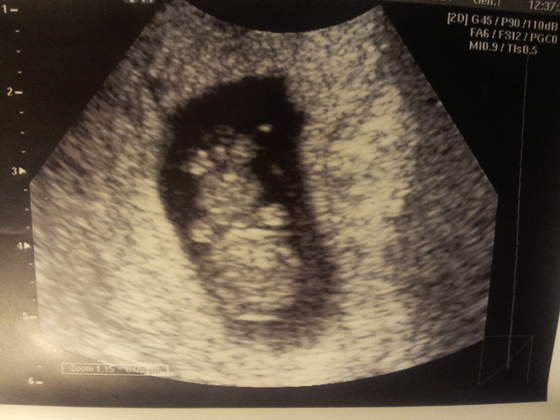

Jejku jakie te maluszki już fajne są

Nanulika gratuluje udanej wizyty, sliczny maluch

eklerkaa piekne malenstwo

eklerkaa słodkie zdjęcie

aha i na usg genetyczne idę ostatecznie do swojego lekarza w pon na 16:30, ale po wczorajszym badaniu boje się mniej bo widziałam mózg, raczki, palce, dłuuuuuuuuuuuuuuuuugaśne nogi, więc jestem spokojniejsza